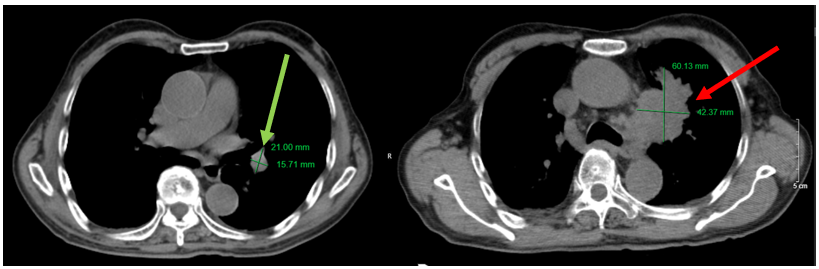

Hình 6. Hình ảnh khối u phổi trái với kích thước 21x16 mm (đang điều trị, mũi tên xanh), tăng kích thước lên 60x42 mm (sau khi bỏ điều trị 3 tháng, mũi tên đỏ) trên phim chụp cắt lớp vi tính lồng ngực, cửa sổ trung thất.

Hình 7. Hình ảnh khối u phổi trái với kích thước 21x16 mm (đang điều trị, mũi tên xanh), tăng kích thước lên 60x42 mm (sau khi bỏ điều trị 3 tháng, mũi tên đỏ) trên phim chụp cắt lớp vi tính lồng ngực, cửa sổ nhu mô.